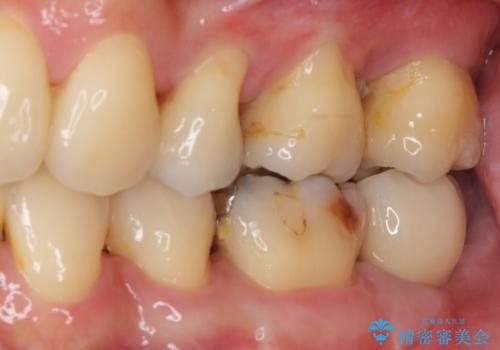

治療期間を短縮することが可能となった、ストローマン社のSLActiveというインプラントを使用し、抜歯からクラウンが装着されるまで6ヶ月という短期間で終えることができました。

咬み心地はもちろん、清掃性もご自分の歯とほとんど変わらない状態となり、患者様には大変満足していただきました。